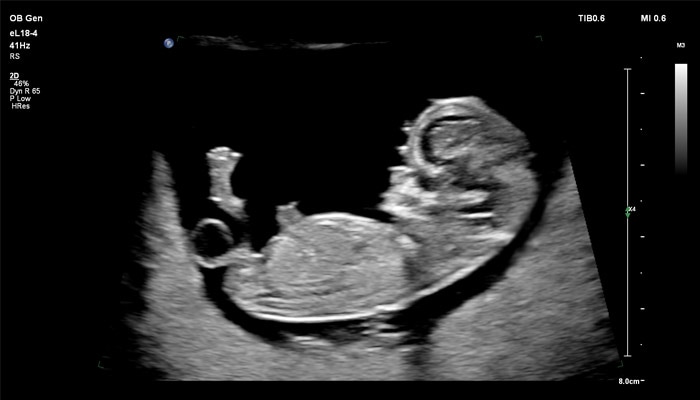

Линейный матричный датчик eL18-4 позволяет получить детальную информацию об анатомии плода и выявить пороки на ранней стадии развития. Сверхширокополосная PureWave матрица датчика генерирует частоты в диапазоне 2-22 МГц, что формирует одинаково высокоинформативные, четкие изображения по всей глубине сканирования до 14 см.

Высокочастотный датчик Philips eL18-4 содержит решетку из 1920 активных монокристаллических пьезоэлементов, выполненных по усовершенствованной технологии PureWave. Это обеспечивает высокодетальную 2D визуализацию, которая в совокупности с глубиной сканирования необходима для уверенной диагностики в акушерстве.

До введения высокочастотных линейных датчиков точная ультразвуковая диагностика мочевой системы плода была доступна в основном после 16-17 недель беременности. Новая технология еL18-4 позволяет проводить раннюю морфологическую оценку плода уже в первом триместре. Клинический случай с применением eL18-4 демонстрирует, что кортико-медуллярная дифференцировка почек плода возможна на 14 неделе беременности”.

Использование линейного матричного датчика eL18-4 при осмотре беременных в I триместре, особенно на ранних сроках, позволяет ограничиться трансабдоминальным сканированием вместо трансвагинального и при этом получить максимально полную диагностическую информацию. Отсутствие полостного исследования чрезвычайно важно для соблюдения принципа ALARA – использования минимальной необходимой мощности для безопасности пациента. Благодаря применению мультичастотного датчика с диапазоном от 2 до 22 МГц через переднюю брюшную стенку хорошо определяется эмбрион длиной 3 мм, что соответствует шестой неделе беременности. В конце I триместра с eL18-4 достаточно отчётливо визуализируется четырёхкамерный срез сердца, мочевой пузырь и сосуды пуповины, которые, как правило, определяются только при трансвагинальном сканировании.

Во II триместре беременности высокая разрешающая способность eL18-4 позволяет детально изучить структуру органов и тканей и увидеть многие нюансы, которые при работе другими датчиками не обнаруживались или становились очевидны в более поздние сроки. Например, у 19-недельного плода визуализируется перегородка носа, мышцы языка, диафрагма между грудной и брюшной полостью, на 20-й неделе чётко определяются оболочки спинного мозга и уретра, а на 24-й – хорошо дифференцируются корень лёгкого, борозды и извилины мозжечка и многие другие структуры.